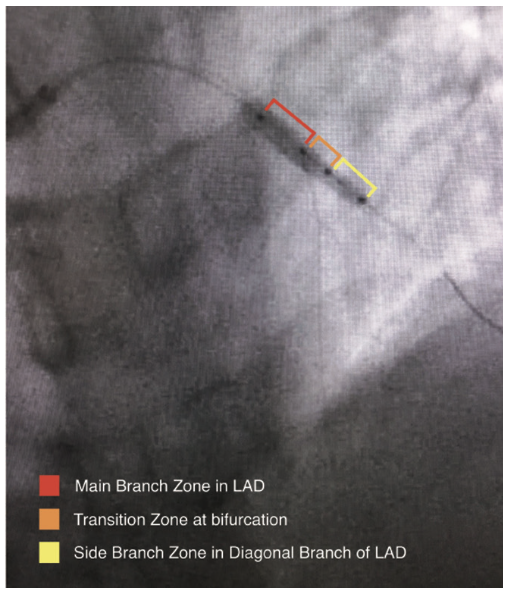

The Tryton side branch stent (Cordis, A Cardinal Health company) is the first FDA-approved stent designed specifically for bifurcation lesions. The specialized design of the Tryton stent has three distinct zones demarcated with radiopaque markers for proper placement at the side branch, which allows for minimal metal-to-artery ratio in the proximal segment and ease of integration of the traditional drug-eluting stent (DES) in the main vessel (Figure 2).2 In this report, we describe a novel utilization of the CorPath GRX robotic heart catheterization system for precise placement of a Tryton side branch stent.

The treatment of bifurcation lesions with percutaneous intervention continues to present a unique challenge to interventional cardiologists. Due to the geometric limitations of traditional drug-eluting stents, the procedure often requires additional time and can be technically difficult. Treatment of bifurcations has been traditionally performed with various techniques, using traditional stents, but each strategy has its own advantages and limitations, and no technique is suitable for every lesion. Several creative methods have been employed, including provisional stenting, V-stenting, simultaneous kissing stent double barrel technique, the crush technique, T-stenting, and the culotte technique, each with its specific advantages and limitations. The common practice of provisional stenting is often susceptible to complications such as restenosis of the side branch. Other stenting techniques using traditional stents can create problems with complete lesion coverage and increased metal-to-artery ratio in the proximal segment.3 As interventionalists search for more definitive treatment of these common lesions, there have also been reports of modifications of the above techniques from various approaches, such as a recently described modified crush technique from a radial approach.4 The Tryton side branch stent, which was also placed using a radial approach in this case, incorporates a Tri-Zone technology design with a specially sized side branch zone, a transition zone for full coverage of the ostium with proper placement, and a main branch zone with minimal metal-to-artery ratio for easier rewiring of the main vessel in order to integrate a DES. These zones are demarcated with radiopaque markers to aid in precise placement at the side branch prior to rewiring the main branch. Accurate placement of the Tryton stent is paramount for full vessel coverage of the side branch with the side branch zone, while keeping the ostium of the main branch open for efficient rewiring and placement of traditional DES.5